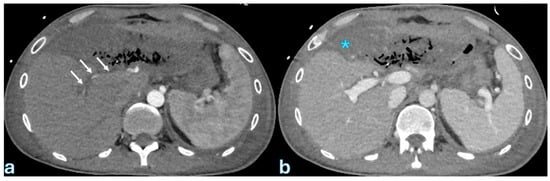

7. Postoperative Pancreatic Fistula

With an incidence ranging from 13% to 41%, postoperative pancreatic fistula (POPF) is the most common complication after pancreatic surgery and a major contributor to morbidity and mortality [141]. It is characterized by a detectable drain output that happens on or after the third postoperative day and an amylase concentration that is more than three times the typical serum level [20,22,41]. POPF can result in intra-abdominal abscesses and, in extreme situations, subsequent bleeding. It is caused by the leakage of pancreatic secretions at an anastomotic site or surgically removed surface. A tiny pancreatic duct, soft pancreatic texture, high-risk underlying disease, and substantial intraoperative blood loss are some of the variables that predispose individuals to POPF. Three grades of POPF are distinguished by the International Study Group of Pancreatic Fistula (ISGPF) [20]: Grade A, which is a biochemical leak without clinical symptoms; Grade B, which is defined by persistent drainage that lasts longer than three weeks and necessitates additional interventions like surgical or percutaneous drainage or presents complications like bleeding or infection; and Grade C, which requires reoperation and is linked to organ failure or death. For the purpose of directing management tactics and reducing serious difficulties, accurate classification is crucial.

Although the best time and indications for postoperative CT are still unknown, contrast-enhanced computed tomography (CECT) is the principal imaging modality used to diagnose POPF. The incidence of serious complications does not seem to be considerably impacted by routine early CT imaging during the first postoperative week. A structured methodology for early complication detection was recently presented by the PORSCH experiment [142]. It suggests CT scans based on clinical and laboratory indicators, including physical examination, changes in drain output, and blood test variations. According to a retrospective investigation, CECT on the seventh postoperative day provided an 83% specificity and 63% sensitivity for identifying POPF. Fluid collections close to the pancreaticojejunostomy site or resection margin, as well as obvious anastomotic disruption, are imaging characteristics diagnostic with Grade B or C POPF. The diagnosis is further supported by certain patients that exhibit aberrant connection with the main pancreatic duct.

Key CT features that differentiate severe (Grade C) POPF from milder cases (Grades A/B) were identified in a study by Lee et al. [143] that involved 235 postoperative patients. These features included acute necrotic collections, which indicated a more severe inflammatory process; pancreaticojejunostomy defects, which indicated incomplete or failed anastomosis; and pancreaticojejunostomy dehiscence, which is defined as a separation of >2 mm between the pancreatic duct and jejunal mucosa (Figure 3).

Secondary complications such as bleeding, pancreatitis, abscess development, and sepsis can also result with POPF; for proper clinical therapy, these conditions need to be carefully assessed on post-contrast CT [48,144]. The type of surgical treatment, the nature of the pancreatic lesion, the postoperative course, and individual patient factors are among the risk factors for postoperative pancreatic fistula that have been discovered. With an emphasis on body composition metrics and pancreatic parenchymal characteristics, recent research has examined preoperative CECT data to forecast POPF risk. Increased pancreatic gland thickness, pancreatic texture and borders, and a larger main pancreatic duct width are specific imaging markers linked to an increased risk of clinically severe POPF. Because pancreatic attenuation values may indicate underlying parenchymal fibrosis, they have also been linked to POPF risk. Furthermore, sarcopenia and visceral obesity have been associated with a higher risk of POPF, indicating that postoperative outcomes may be influenced by muscle and metabolic state [145,146]. By identifying these preoperative imaging indicators, surgical planning can be improved and risk can be stratified, which will ultimately lower the frequency and severity of postoperative pancreatic fistula.